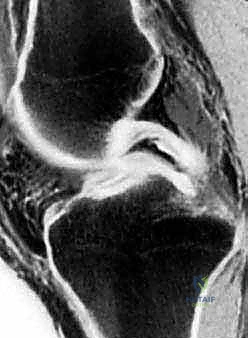

- التصوير بالرنين المغناطيسي (MRI): هو المعيار الذهبي (Gold Standard) لتشخيص تمزقات الغضروف الهلالي. يوفر صوراً ثلاثية الأبعاد وعالية الدقة للأنسجة الرخوة. من خلال الرنين، يستطيع الدكتور هطيف تحديد نوع التمزق، حجمه، موقعه (في أي منطقة دموية)، وما إذا كانت هناك إصابات مصاحبة (مثل تمزق الرباط الصليبي الأمامي ACL).

يقوم الجراح بفحص الغضروف الممزق باستخدام أداة مسبار (Probe) دقيقة. يتم تقييم حجم التمزق، موقعه، ونوعية الأنسجة. إذا كان التمزق في المنطقة الدموية (الحمراء) والأنسجة جيدة، يُتخذ القرار فوراً بـ "الإصلاح والخياطة".